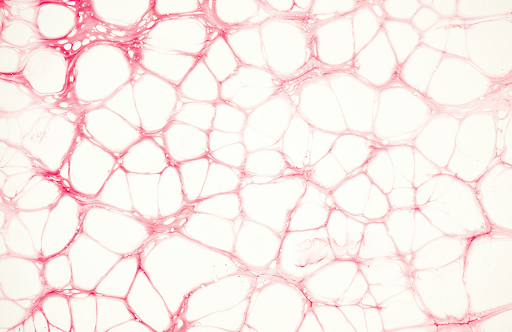

毛细血管扩张(也称毛细血管破裂)是指出现在皮肤表面附近的细小扩张血管,常见于鼻子、脸颊和下巴。虽然它们本身无害,但对许多人来说,却会影响美观。

激光治疗利用聚焦光能精准作用于受损毛细血管,加热使其破裂。随着时间的推移,人体会自然吸收这些被治疗过的血管,从而使皮肤更加光滑细腻。